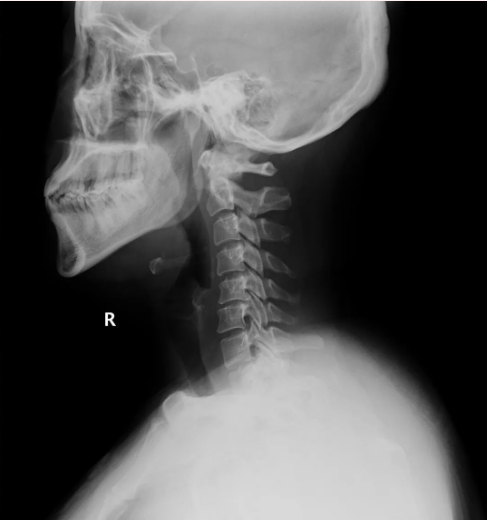

“神经内科、神经外科、心内科、五官科都看了,不是这些原因导致的!”29岁的小吴带着一摞检查单走进疼痛科,经过专科专业检查,终于揪出导致他头痛难忍的真凶——竟是颈椎惹的祸!统计显示,颈源性头痛的发病率呈现出逐年递增的趋势,并且低龄化越来越明显。

颈神经线分布在人体的颈椎区域,负责传递来自头部、颈部、肩膀以及上肢的感觉和运动信号,通常分为8对,从C1到C8。C1-C3神经像”电线”一样连接头部,当颈椎退变、肌肉劳损或受凉时,这些”电线”短路会引发放射性头痛,如同电线短路引发跳闸,颈椎问题会导致神经”错乱放电”,从而引起头痛等问题。

核磁显示颈椎曲度变直/增生